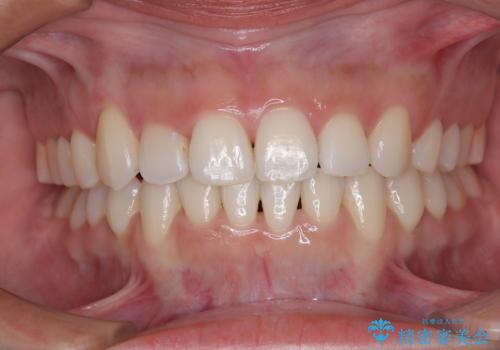

- 上下前歯のデコボコを気にして来院された患者様です。

上顎歯列が下顎の歯列に対して狭小であり、一部下顎の奥歯が上顎よりも外側に位置している状態でした。

上顎の急速拡大装置を使用して上顎骨を側方に拡大することで上顎歯列を拡大し、下顎歯列も拡大できるようにすることで、歯列を整えることとしました。

歯列矯正では基本的に骨格を改善することはできませんが、急速拡大装置(MARPE)を使用することで上顎骨を側方に拡大させることができ、咬合状態を大きく改善することができます。